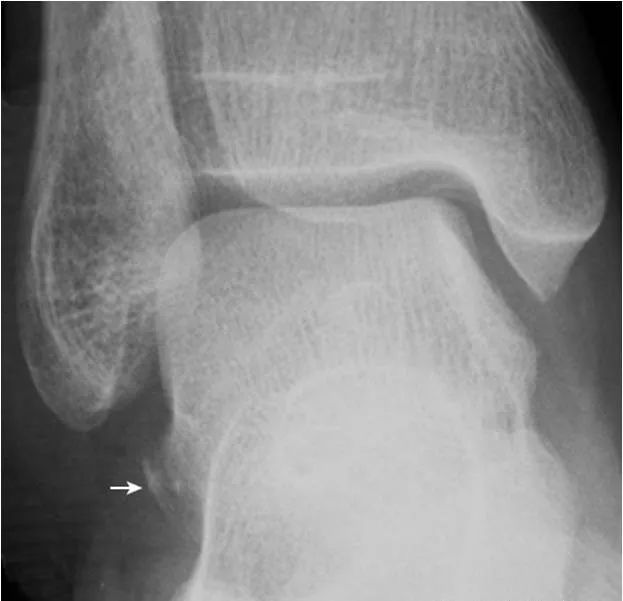

5.楔舟内侧骨:

内侧楔骨与足舟骨之间的内侧,可见小的骨性结节(箭),为正常变异。需与撕脱骨折鉴别。另可见舟骨副骨(箭头)。

6.楔骨间骨:

为内侧及中间楔骨间副骨,边缘光滑(箭),属正常变异。内侧楔骨前内缘致密影(双箭头)为胫骨前肌肌腱附着处后缘的切线位投影,非病变。内侧楔骨与舟骨间见楔舟内侧骨(箭头)。